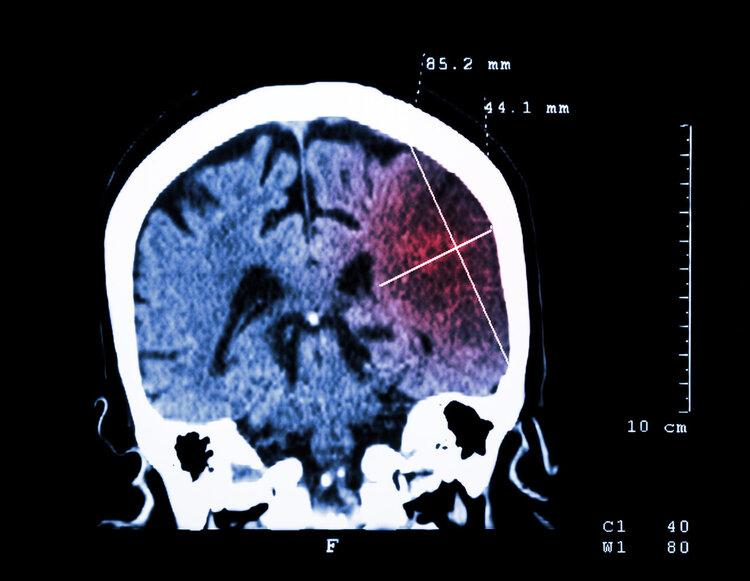

經檢查大爺血壓高達180mmHg,結合大爺有高血壓病史,又出現口角歪斜、肢體無力等表現,最後診斷爲腦出血,需要立刻手術降壓。醫生提醒這已經不是第一個因爲高血壓引發腦出血的病例了。